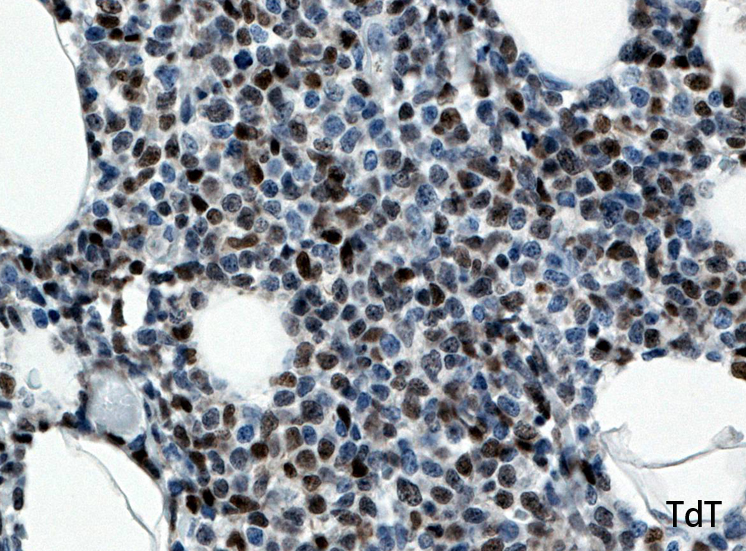

TdT.jpg

CD56CD123TdT